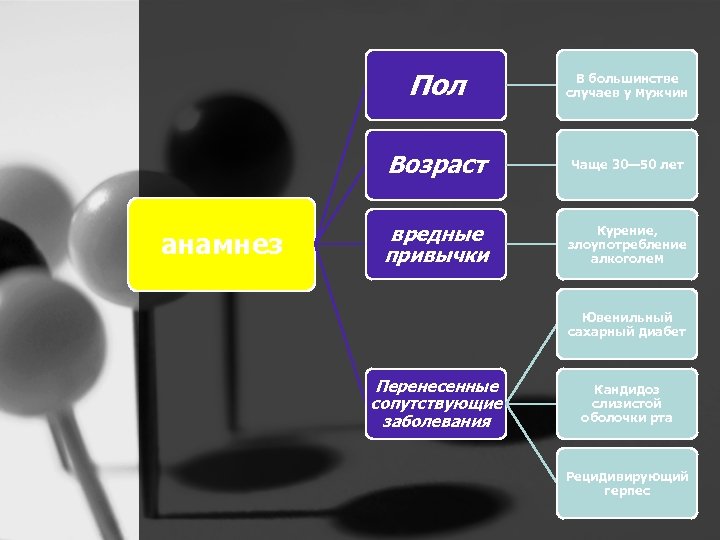

Пол Возраст анамнез В большинстве случаев у мужчин Чаще 30— 50 лет вредные привычки Курение, злоупотребление алкоголем Ювенильный сахарный диабет Перенесенные сопутствующие заболевания Кандидоз слизистой оболочки рта Рецидивирующий герпес